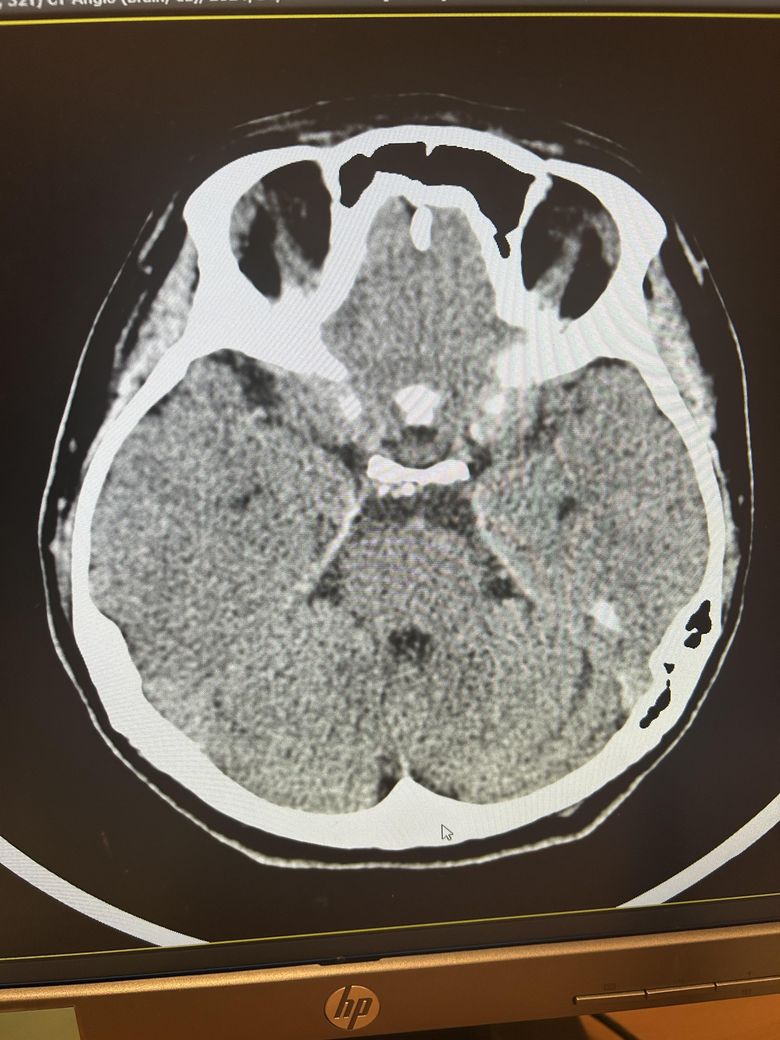

두통과 목뻐근함이 일주일째 심해서 뇌ct검사를 했습니다.

영상은 이렇게 보이는데 어떻게 의심되시나요?

석회화랑 다른것도 보이시나요?